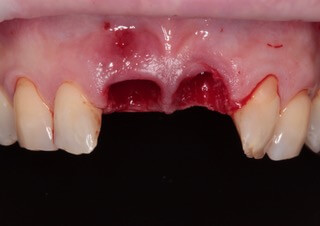

Do známeho českého časopisu Implants sme prispeli kapitolou, v ktorej Dr. Michal Repaši popisoval klinický prípad navigovanej chirurgie z praxe. Išlo o 45 ročnú pacientku, ktorá sa obrátila na našu kliniku s bolesťou v oblasti horných stredných rezákov. Pri dôkladnom vyšetrení a CT diagnostike bola v oblasti zuba č. 11 zistená vertikálna fraktúra koreňa. V oblasti zuba č. 21 palatinálne bol prítomný hlboký kaz koreňa.

Jediným riešením bola extrakcia obidvoch zubov. Najväčšou obavou zo strany pacientky bola strata obidvoch predných zubov a následného fungovania bez nich pri práci s ľuďmi.

V ďalšom kroku sme virtuálne vložili implantáty v správnej protetickej polohe, navrhli šablónu pre ich zavedenie, namodelovali individuálne abutmenty a korunky. Kompletné dáta sme exportovali pre frézovanie a 3D tlač. V laboratóriu sa pomocou 3D tlačiarne vytlačila chirurgická šablóna, ktorá nám slúži na presné zavedenie implantátov – použili sme implantačný systém Dentium Super Line. Následne boli vyfrézované zirkonové abutmenty a plastové dočasné korunky.

Ukážka - navigovaná chirurgia z praxe